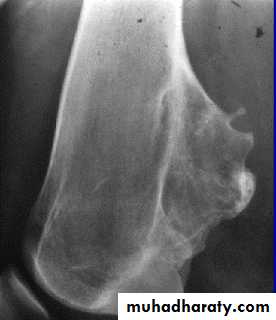

(Intermediate tumors)Giant cell tumor (osteoclastoma):

Pathology:

This tumor contains multinucleated giat cells and large number of stromal cells.

Its soft friable tumor seen in the soft cancellous subarticular bone and never reach the articular surface.

represents 5 per cent of all primary bone tumours, is a lesion of uncertain origin that appears in mature bone, most commonly in the distal femur, proximal tibia, proximal humerus

It’s a tumor of young adults occurs after bone maturity in the epiphysial region.

Its intermediate type of tumor (neither benign nor malignant)

About 1/3 of it remains benign ,

1/3 is locally aggressive,

1/3have distant metastasis.

Clinical features:

Patient aged 20-40.

There is pain or swelling near a joint, 10% presents with pathological fracture.

O/E vague swelling at the bone end and signs of joint irritation.

X-ray:

Rarefied area of the bone end reaching just below the articular surface.

Eccentrically situated lesion with bone expansion and ballooning with cortical thinning, sometimes pathological fracture.

There may be calcific trabiculations inside the lesion giving it the commonly known saop-bubble appearance.

Treatment:

For well-defined small and rather benign lesion, we can do curettage and burr-down with bone graft.

Larger more aggressive lesions may need local excision and bone graft or prosthetic replacement.

GCT treated with local excision and bone graft